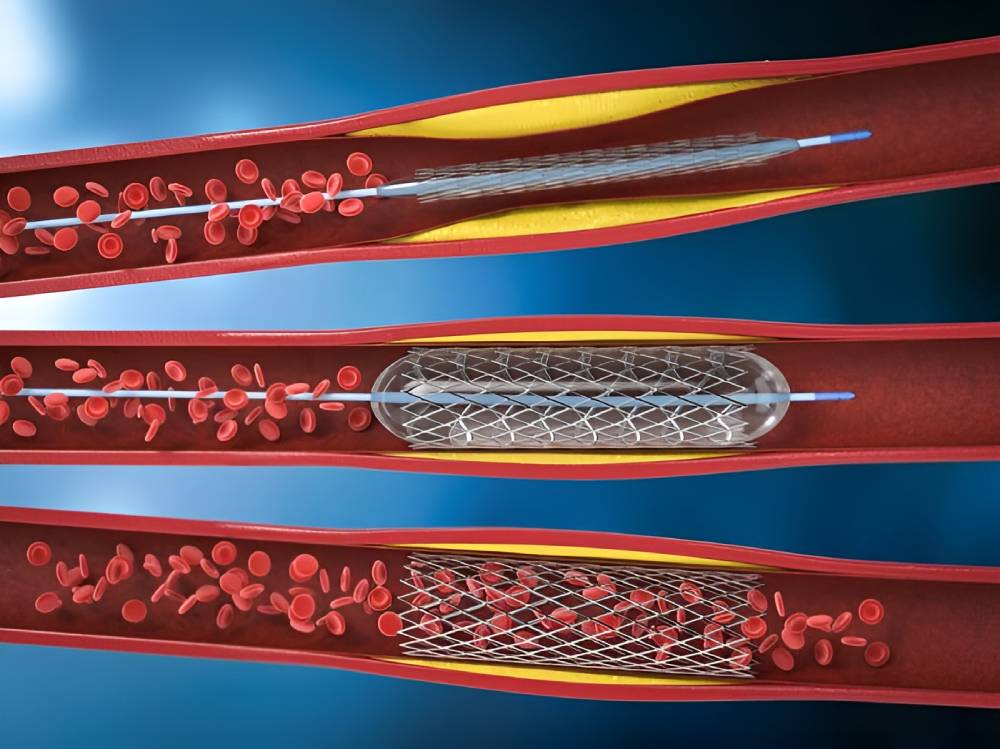

آنژیوپلاستی

اصطلاح «آنژیوپلاستی» به معنای استفاده از بالن برای باز کردن شریان مسدود یا تنگ است. البته در اکثر عملهای آنژیوپلاستی مدرن لولۀ توری سیمی کوتاهی به نام استنت وارد شریان میشود. استنت برای همیشه در شریان باقی میماند تا خون راحتتر جریان پیدا کند.

مراحل انجام آنژیوپلاستی

آنژیوپلاستی قلب با استفاده از بیحسی موضعی انجام میشود، بنابراین بیمار در طول عمل هوشیار است.

متخصص قلب برشی را روی کشالۀ ران، مچ دست یا بازو ایجاد میکند و لولۀ باریک و منعطفی به نام کاتتر را از راه این برش وارد یکی از شریانها میکند. متخصص کاتتر را با توجه به فیلم رادیوگرافی به سمت شریان کرونری درگیر هدایت میکند.

وقتی کاتتر در جای مناسب قرار گرفت، متخصص قلب سیم نازکی را در تمام طول شریان گرفته پایین میبرد و بالن کوچکی را در بخش گرفتۀ شریان قرار میدهد. سپس بالن را باد میکند تا شریان گشاد شود و رسوبات چربی چسبیده به دیوارهی شریان متلاشی شوند. به این ترتیب وقتی متخصص باد بالن را خالی میکند و آن را بیرون میکشد، خون راحتتر جریان پیدا میکند.

اگر از استنت استفاده شود، استنت پیش از جایگذاری دور بالن قرار دارد. وقتی بالن باد میشود، استنت منبسط میشود و پس از خالی کردن باد بالن و بیرون کشیدنش همانجا باقی میماند.

آنژیوپلاستی کرونری معمولاً ۳۰ دقیقه تا دو ساعت طول میکشد. اگر آنژیوپلاستی برای درمان آنژین انجام شود، معمولاً همان روز چند ساعت بعد یا فردای روز عمل مرخص میشوید. بلند کردن بارهای سنگین، فعالیتهای بدنی شدید و رانندگی به مدت حداقل یک هفته ممنوع است.

گاهی اوقات آنژیوپلاستی با لیزر انجام میشود. در این حالت سر کاتتر مجهز به لیزری است که شریان مسدود را باز میکند. متخصص کاتتر ساطعکنندۀ لیزر را در آنژیوپلاستی لیزری وارد بخش گرفتۀ شریان میکند. سپس لیزر را روشن میکند تا لیزر پلاک را تبخیر کند و در نتیجه گرفتگی شریان کمتر شود.

مطالعۀ منتشرشده در سال ۲۰۲۱ حکایت از آن دارد که آنژیوپلاستی با لیزر احتمال بروز عوارض را افزایش میدهد و به همین دلیل کمتر انجام میشود. آنژیوپلاستی با لیزر غالباً برای درمان انسداد مجدد کاربرد دارد؛ در این حالت گرفتگی شریانها پس از انجام آنژیوپلاستی معمول با استنت عود میکند.